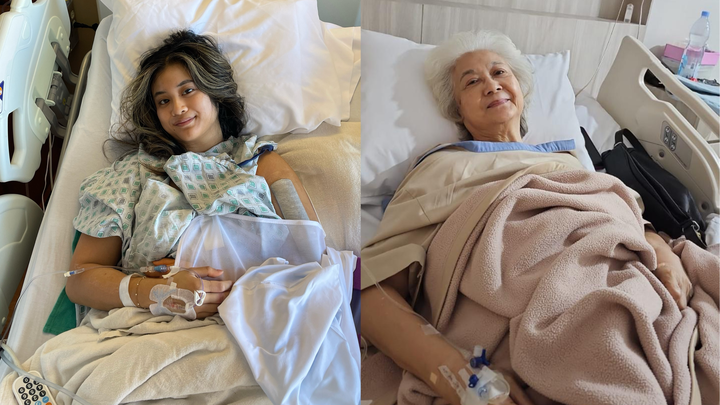

On January 26, my sister fell and broke her arm in New York a few days before our mom was supposed to fly in from Jakarta, Indonesia. On January 28, my grandma fell and broke her leg in Jakarta. Both required surgery and hospitalization.

Torn between her daughter in New York and her mother in Jakarta, it was ultimately decided that my mom would go through with her trip to take care of her daughter while remotely arranging for care for her mother.

My sister and grandma's surgeries were successful but also very costly (especially if we include the extensive physical therapy they would both have to go through). My mom bears the majority of our family's financial responsibilities. She is a single mother who has to work 70+ hours a week to support her family, acting as our grandma's main caretaker and regularly helping both me and my sister when our own income falls short of making rent.